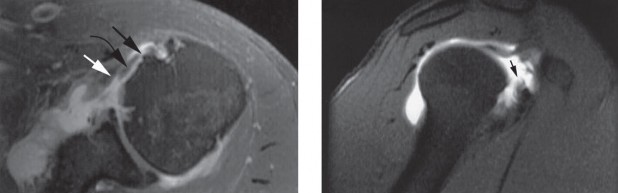

Magnetic Resonance Imaging (MRI) is the gold standard for evaluating rotator cuff pathology. On T2-weighted sequences, a partial-thickness tear appears as a focal region of hyperintensity that does not traverse the entire tendon substance. For articular-sided tears, Magnetic Resonance Arthrography (MRA) provides superior sensitivity and specificity. The intra-articular contrast distends the joint and readily enters articular-sided defects. The ABER (Abduction and External Rotation) view on MRI is particularly useful for visualizing articular-sided tears and assessing internal impingement.

A standard posterior viewing portal is established. A thorough diagnostic arthroscopy of the glenohumeral joint is performed. The articular surface of the rotator cuff is inspected. An articular-sided partial tear (often referred to as a PASTA lesion - Partial Articular Supraspinatus Tendon Avulsion) will present as a detachment of the tendon from the medial footprint.

An anterior portal is established within the rotator interval. An arthroscopic probe is introduced to palpate the tear and assess the quality of the remaining tissue. The critical step is measuring the exposed footprint. A calibrated probe is used to measure the distance from the articular margin of the cartilage to the intact tendon insertion. If the exposed footprint measures greater than 7 mm, the tear is deemed >50% and warrants repair.